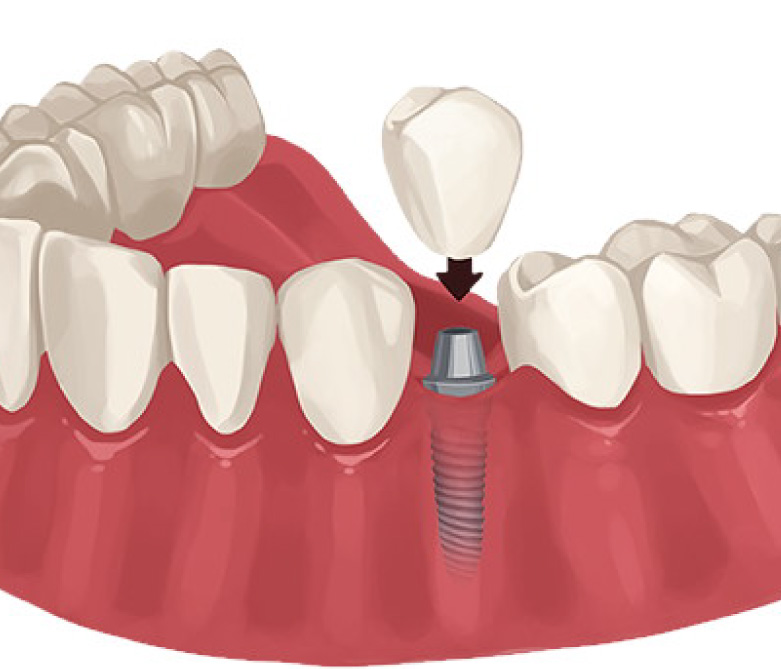

A dental implant is a titanium post surgically placed into the jawbone

to serve as a replacement root for a missing tooth. It supports a

dental crown, bridge, or denture, providing a stable and

natural-looking solution for tooth loss.